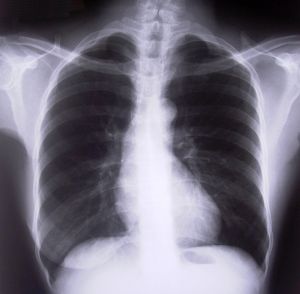

Asbestos in lungs

Mesothelioma